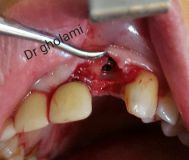

معرفی سیستم SPI همراه با جراحی زنده و Immediate Loading - آبان ۹۵

جراح وسخنران : استاد دکتر غلامعلی غلامی